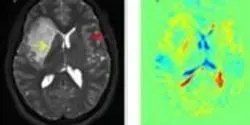

A new tumor-modeling platform called a tumor-microenvironment-on-chip can be used to visualize and quantify how different types of cancer cells react differently to the chemotherapy drug doxorubicin